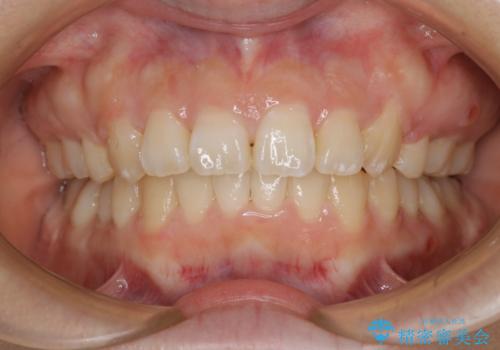

前歯の乱れをスッキリ解消!抜歯矯正で整えた美しい歯並び

担当医 河口智英